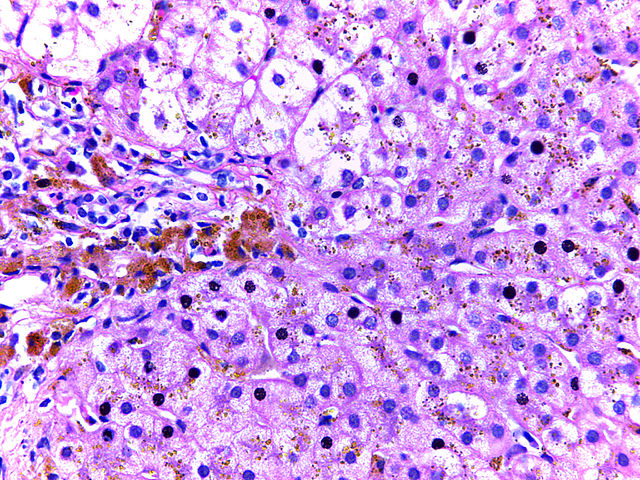

L’hémochromatose est une maladie autosomale récessive qui touche une personne sur mille en France, caractérisée par une accumulation du fer dans le foie, le pancréas, le cœur, les articulations et les gonades. Sans traitement, l’hémochromatose est responsable d’une surmortalité liée au risque de survenue de carcinome hépatocellulaire, des autres complications de la cirrhose, des complications du diabète et de cardiomyopathie.

L'hémochromatose liée au gène HFE, forme la plus fréquente, est due à une production hépatique insuffisante d'hepcidine qui entraîne une hyperabsorption du fer alimentaire, une libération rapide du fer par les macrophages recyclant les érythrocytes sénescents et l’accumulation du fer non lié à la transferrine dans les tissus, notamment le foie. Cette affection est traitée par des phlébotomies itératives (« saignées ») afin de ramener la ferritine en deçà de 50-100 ng/ml.

Dans cette étude menée pour répondre au besoin d'une alternative aux phlébotomies, Kowdley et coll. ont constaté que le rusfertide diminuait en toute sécurité les concentrations du fer sérique, du CST et de fer hépatique, et réduisait le nombre de phlébotomie (par rapport à 24 semaines avant l'étude). Les données de l'essai suggèrent que le rusfertide en l'absence de phlébotomie prévient l'augmentation naturelle du CST chez les sujets atteints d'hémochromatose. De plus, les augmentations de la ferritine médiées par le rusfertide suggèrent une redistribution du fer des cellules parenchymateuses vers les macrophages spléniques, un site de stockage du fer relativement plus sûr.